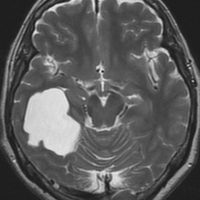

中頭蓋窩・症候性・くも膜のう胞

60代の女性で偶然発見された大きなクモ膜のう胞です。経過とともに少しづつ増大して,ふらつき,眠気,気分の落ち込みなど抑うつ状態となりました。抗うつ薬の投与が開始され増量されましたが精神症状は悪化して何もできなくなりました。おそらく右側頭葉症状として抑うつ症です。内視鏡ですと脳に損傷が生じますから,開頭顕微鏡手術で,クモ膜のう胞を脳底槽へ開窓しました。術後に症状は消失して5年になりますが,抗うつ薬なしで元気にしています。

もしかするとこれは,巨大な choroidal fissure cystかもしれません。